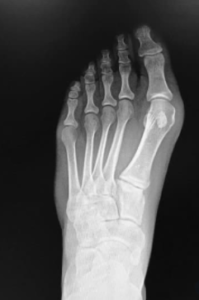

Ο βλαισός μέγας δάκτυλος ή αλλιώς ΄΄κότσι΄΄ αποτελεί την πιο συχνή παραμόρφωση του ποδιού. Συγκεκριμένα, παρατηρείται απόκλιση του 1ου δακτύλου προς το δεύτερο δάκτυλο. Ο πόνος εμφανίζεται στην 1η μεταταρσοφαλαγγική άρθρωση και ιδιαίτερα κατά την φόρτιση του 1ου μεταταρσίου στην διάρκεια της βάδισης και κατά την εφαρμογή υποδημάτων.

Ο βλαισός μέγας δάκτυλος ορίζεται όταν το μέγεθος της γωνίας μεταξύ του 1ου μεταταρσίου και της εγγύς φάλαγγας του 1ου δακτύλου είναι μεγαλύτερη των 15 μοιρών και ταξινομείται σε 3 κατηγορίες:

- Ήπια κατάσταση 15-20ο

- Μέτρια κατάσταση 20-39ο

- Σοβαρή κατάσταση >40o